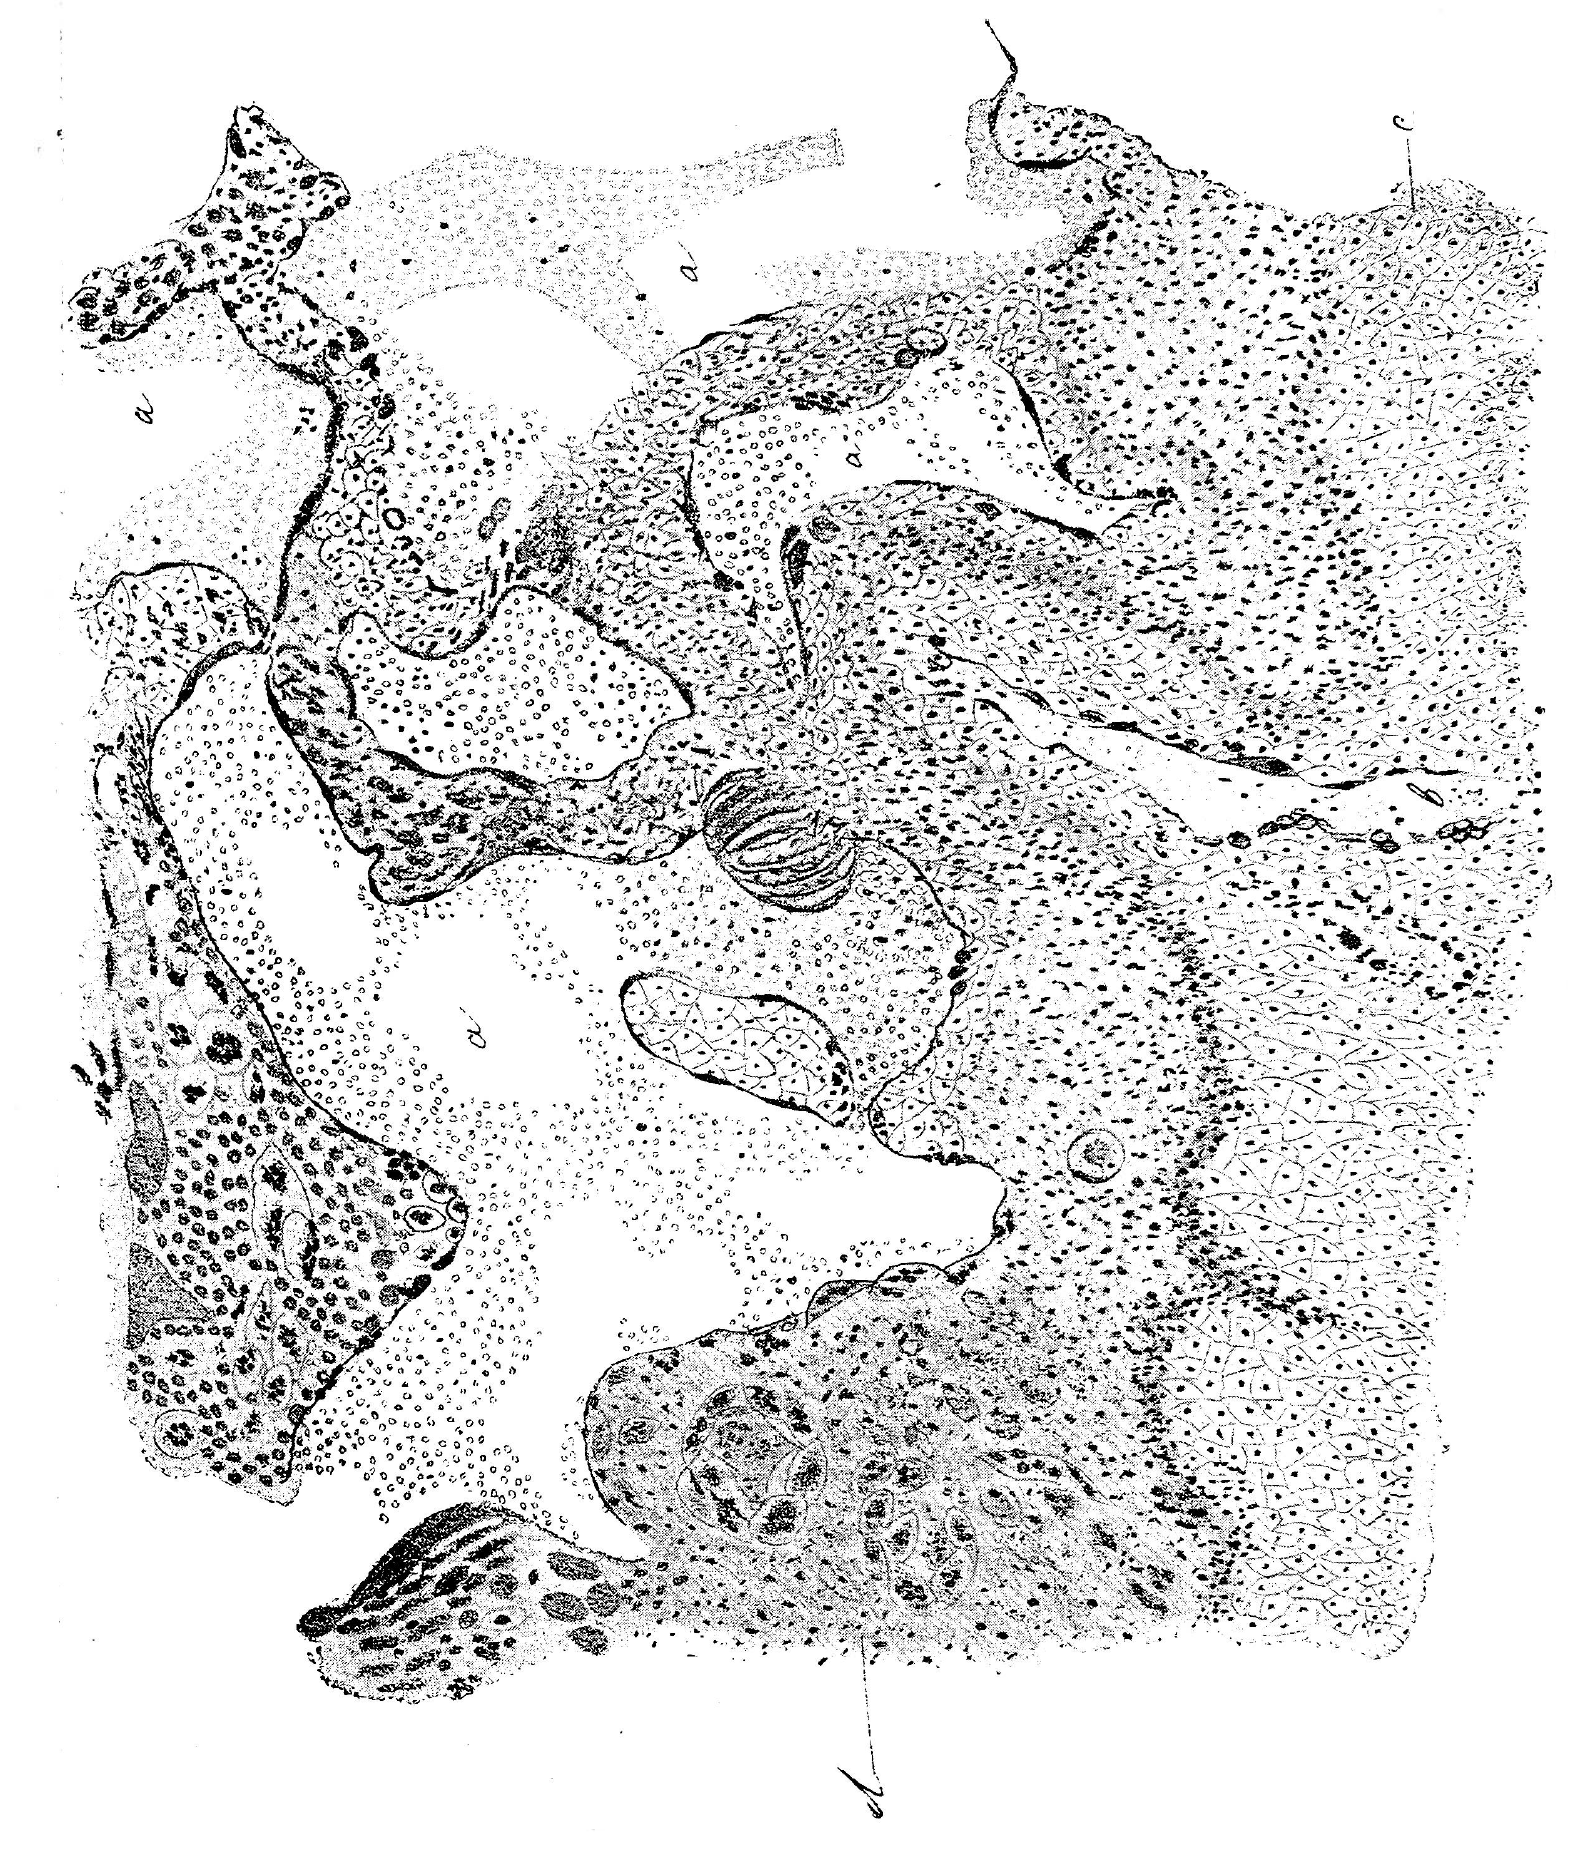

Какъ на особенность этого отдѣла беременнаго рога кролика, слѣдуетъ указать на присутствіе особаго рода клѣтокъ, впервые описанныхъ Minot, подъ именемъ Monsterzells. Это гигантскія клѣтки sui generis (рис. 14 а и b). На разрѣзахъ тѣло ихъ колеблется въ размѣрахъ и бываетъ иногда такъ велико, что занимаетъ собою сплошь все пространство между сосѣдними железами. Форма гигантовъ разнообразная. Протоплазма ихъ гомогенная или нѣжно-зернистая, при тонкой обработкѣ (Флеммингъ) вся поверхность ея точно исчерчена тонкими кружечками. Какой-либо клѣточной оболочки не существуетъ. Въ клѣткѣ лежитъ одно, рѣже два колоссальныхъ же ядра овальной или круглой формы; нельзя не замѣтить, что оно имѣетъ будто свою оболочку, въ которой лежитъ нѣсколько крупныхъ же ядрышекъ (величиною равныхъ ядрамъ элементовъ сосѣднихъ тканей). Чаще ядра находятся въ состояніи распаденія, хроматолиза; получаются зерна, зернышки, комочки различной формы и палочки — все это густо окрашивается. Обработывая свѣжій препаратъ 30% растворомъ ѣдкаго кали и расщепляя его иглами по истеченіи нѣсколькихъ минутъ, удается изолировать гиганты. Онѣ такъ велики, что на микроскопическихъ срѣзахъ не могутъ попасть цѣликомъ. Изолированныя онѣ имѣютъ видъ колоссальныхъ колбъ и мѣшковъ, съ однимъ, рѣже двумя толстыми же отростками на противоположныхъ концахъ. Совершенно отдѣлить ихъ отъ окружающей соединительной ткани или сосѣднихъ сосудовъ не удается. Послѣдніе точно спаяны съ ними. Вся поверхность протоплазмы гигантовъ усѣяна нѣжными контурами кружечковъ.

Рис. 14. Гиганты или Monsterzells Minot.

Fig.: 14. Giants or Monsterzells Minot.

Изучая цѣлый рядъ препаратовъ при различной обработкѣ, не трудно убѣдиться, что передъ нами ничто иное, какъ особеннымъ образомъ перерожденныя железы. Дѣйствительно, на препаратахъ отчетливо видно, какъ клѣтки железъ разбухаютъ, дѣлаются гомогенными и сливаются между собою до полнаго исчезновенія границъ. Ядра, сохраняя круговое расположеніе, постепенно сдвигаются къ центру и какъ будто заключаются въ особую оболочку.

Это регрессивный метаморфозъ железъ, гибель ихъ. Железы въ беременной маткѣ развиваются такъ усиленно, что углубляясь, заходятъ даже въ мышечный слой, поэтому неудивительно, что и здѣсь встрѣчаются вышеописанные гиганты.

Въ дальнѣйшемъ они разсасываются посредствомъ развивающихся около нихъ кровеносныхъ сосудовъ, что можно видѣть на препаратахъ, болѣе позднихъ стадій беременности.

Рис. 13. Obplacenta: а-измѣненный железистый эпителій, b—железы, c—оторвавшіяся клѣтки железистаго эпителія.

Fig.: 13. Obplacenta: a-altered glandular epithelium, b — glands, c — detached cells of the glandular epithelium.